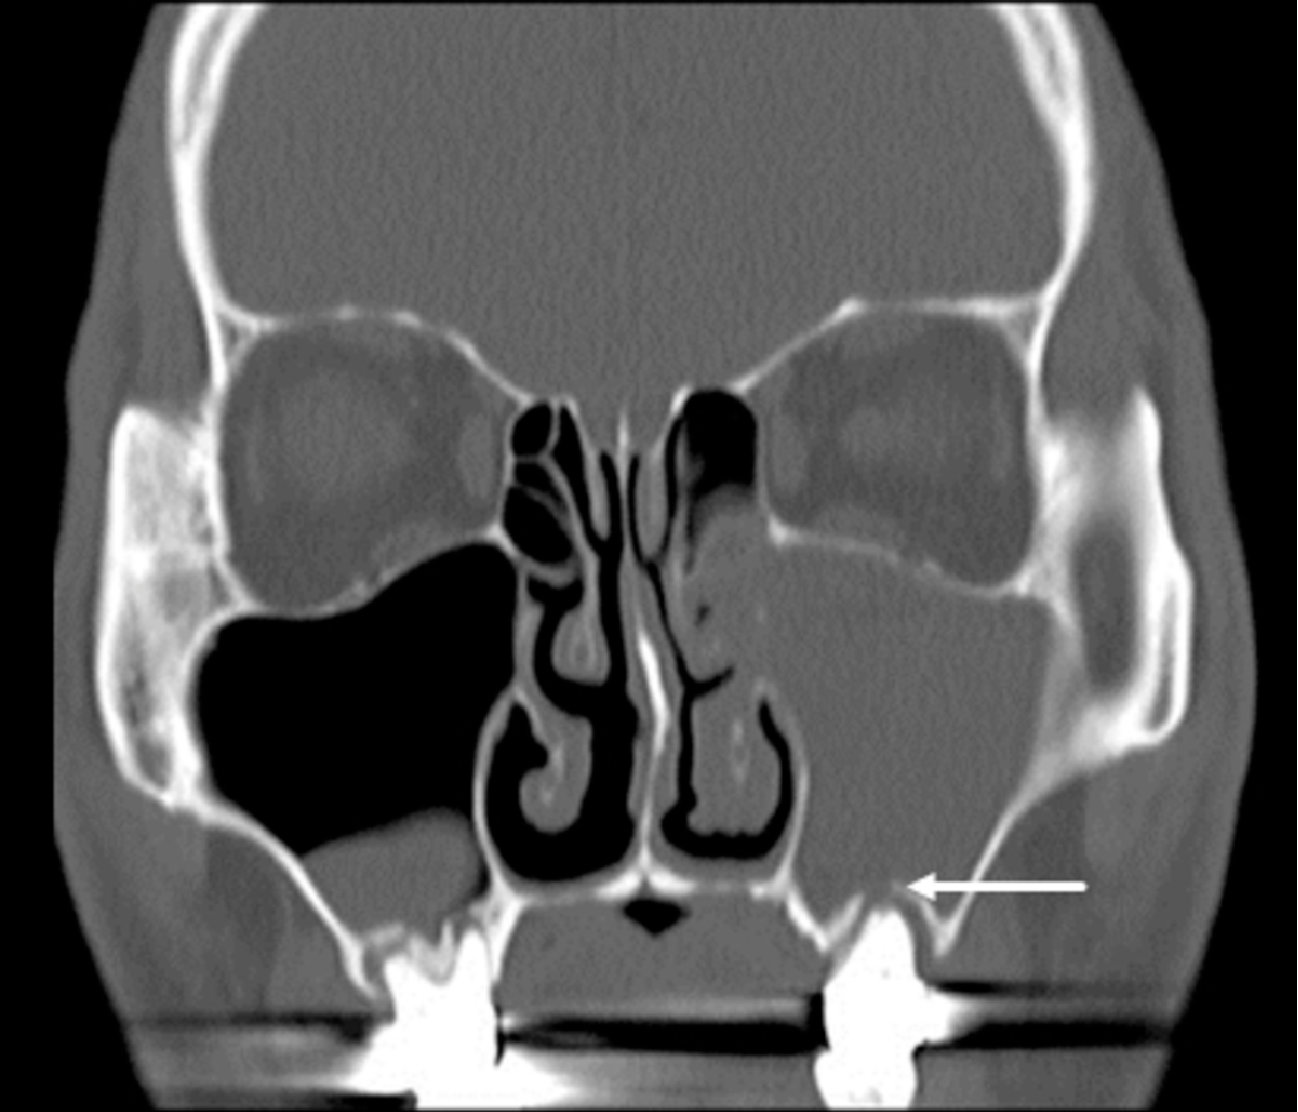

一位患者因反覆鼻竇炎症狀,左側持續流膿黃鼻涕已4年,由耳鼻喉科醫師轉介到牙科評估,經詳細的臨床口內及X光放射影像學檢查,發現患者左上第一大臼齒有一崩壞的暫時填充物,並有齲齒繼續蛀蝕的現象,因為沒有牙痛的症狀,所以患者沒有到牙科求診。後續經過幾次根管治療,根管清創、沖洗和換藥後,患者的膿鼻涕逐漸減少,口內觸診也不再有壓痛感。

上顎後牙因靠近鼻竇底部,因此嚴重的根尖發炎可能引起鼻竇炎症狀,臺北市立聯合醫院和平婦幼院區口腔醫學科醫師葉沛盈指出,齒源性鼻竇炎(odontogenic sinusitis)意指病人患有鼻竇方面之疾病,且此疾病透過影像學、微生物學或是臨床上的證據證實與牙齒相關。

根據文獻統計,齒源性鼻竇炎約佔單側上顎竇鼻竇炎的三成,且近年來,此類和牙科相關的鼻竇炎比例有升高的趨勢,值得大家提高警覺。

其常見的症狀包括惡臭膿黃鼻涕、鼻子經常聞到臭味、臉部疼痛或腫脹感、鼻涕倒流以及鼻塞等。可能引起齒源性鼻竇炎的原因有牙科手術、齒源性感染、異物、齒源性囊腫、口竇管等,當病人診斷為單側鼻竇炎的同時,就必須警覺到齒源性鼻竇炎的可能性。

葉沛盈表示,齒源性鼻竇炎是鼻竇炎中較為特別的一環,需要牙科醫師和耳鼻喉科醫師細心的評估影像學檢查,並且與臨床發現互相配合比較,做出正確的診斷。在治療方面,配合抗生素治療、牙科處理和鼻竇內視鏡手術的使用,通常具有良好的治療效果。